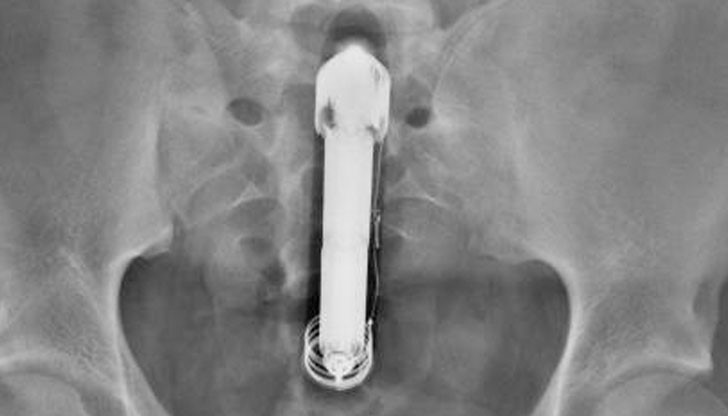

Американец, който страда от остра форма на запек, потърси медицинска помощ заради болки в корема и неспособността си да се изхожда. Мъжът отишъл в спешното отделение в калифорнийския град Фресно заедно със съпругата си.

След кратък преглед лекарите го изпратили в рентгена, за да изследват проходимостта на червата. За изненада на медиците обаче в дебелото черво на пациента ясно се виждал голям заседнал вибратор. При това вибраторът все още била включена.

„Може и да звучи смешно, но ситуацията е крайно неприятна и опасна. Подобна немарливост може да доведе до сериозен вътрешен кръвоизлив, инфекция и тежка коремна операция, придружена от колостомни торбички и интравенозно хранене”, коментират хирурзи, цитирани от изданието. След срамното разкритие съпругата разкрила пред лекарите, че двамата с мъжа й искали да разнообразят сексуалния си живот с малко експерименти. За нещастие ситуацията излязла извън контрол, а играчката за възрастни навлязла дълбоко в мераклията.

Медиците успели да извадят навреме изкуствения пенис, предизвикал прекалено лоши вибрации.